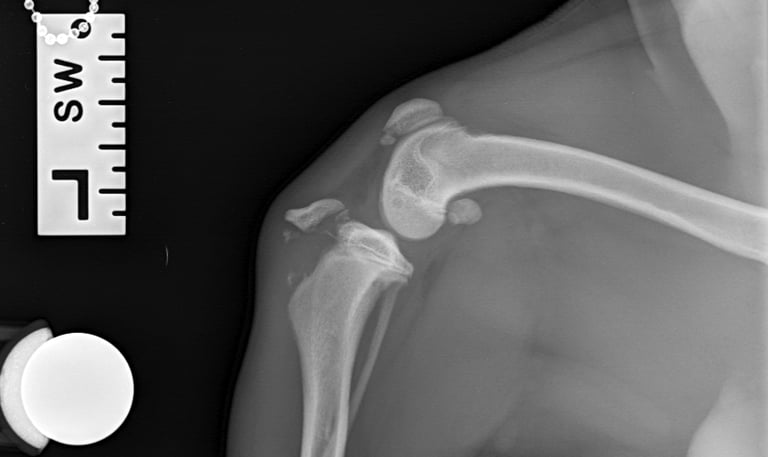

Case 4 - Luna

Cranial Cruciate Ligament Disease CCLD - American Bulldog, 5y, female